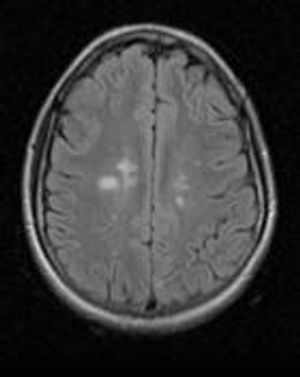

Do you have a patient with "radiologically isolated syndrome" -- and, if so, what do you tell your patient?